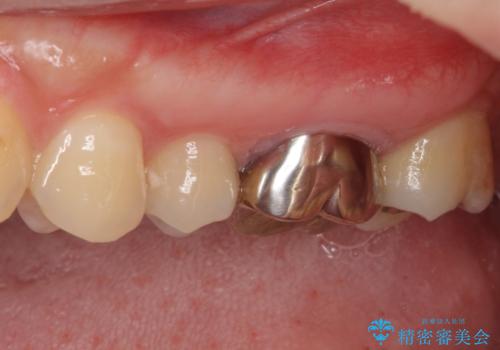

- 奥歯の虫歯と銀歯を気にして来院された患者様です。

セラミックインレーおよびセラミッククラウンによる治療を希望されましたが、虫歯となっている歯は神経近くにまで蝕まれていたため、長期的な予後を鑑みて、PGAインレー(プラチナゴールドインレー)にて修復することとしました。

ゴールドインレーを装着するまでは、金属色が目立ってしまうのではないかと心配されていましたが、表からは見えない位置にあること、銀歯と異なり目立つ色ではないことから、審美的な問題はありませんでした。